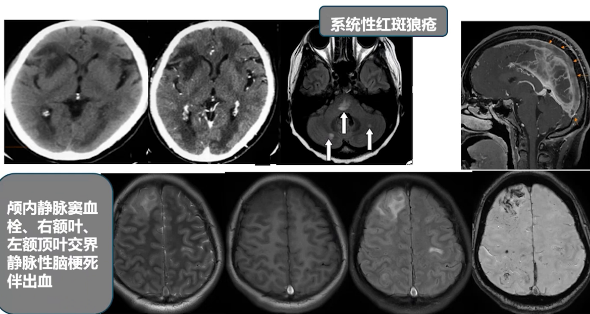

年轻女性脑梗死原因多样,主要包括心源性、血管性、自身免疫性疾病以及凝血异常。心源性如感染性心内膜炎赘生物脱落、风湿性心脏病二尖瓣狭窄导致血栓形成,均可阻塞脑血管引起脑梗死。血管性疾病如烟雾病和血管畸形,作为先天性发育异常疾病,好发于年轻人。自身免疫性疾病中,系统性红斑狼疮在青年女性中较为常见,可导致小脑半球及脑干梗死,且机体处于高凝状态易引发脑梗死。凝血异常方面,以孕产妇产后高凝导致颅内静脉窦血栓形成为例,可出现静脉性梗死伴微量出血。